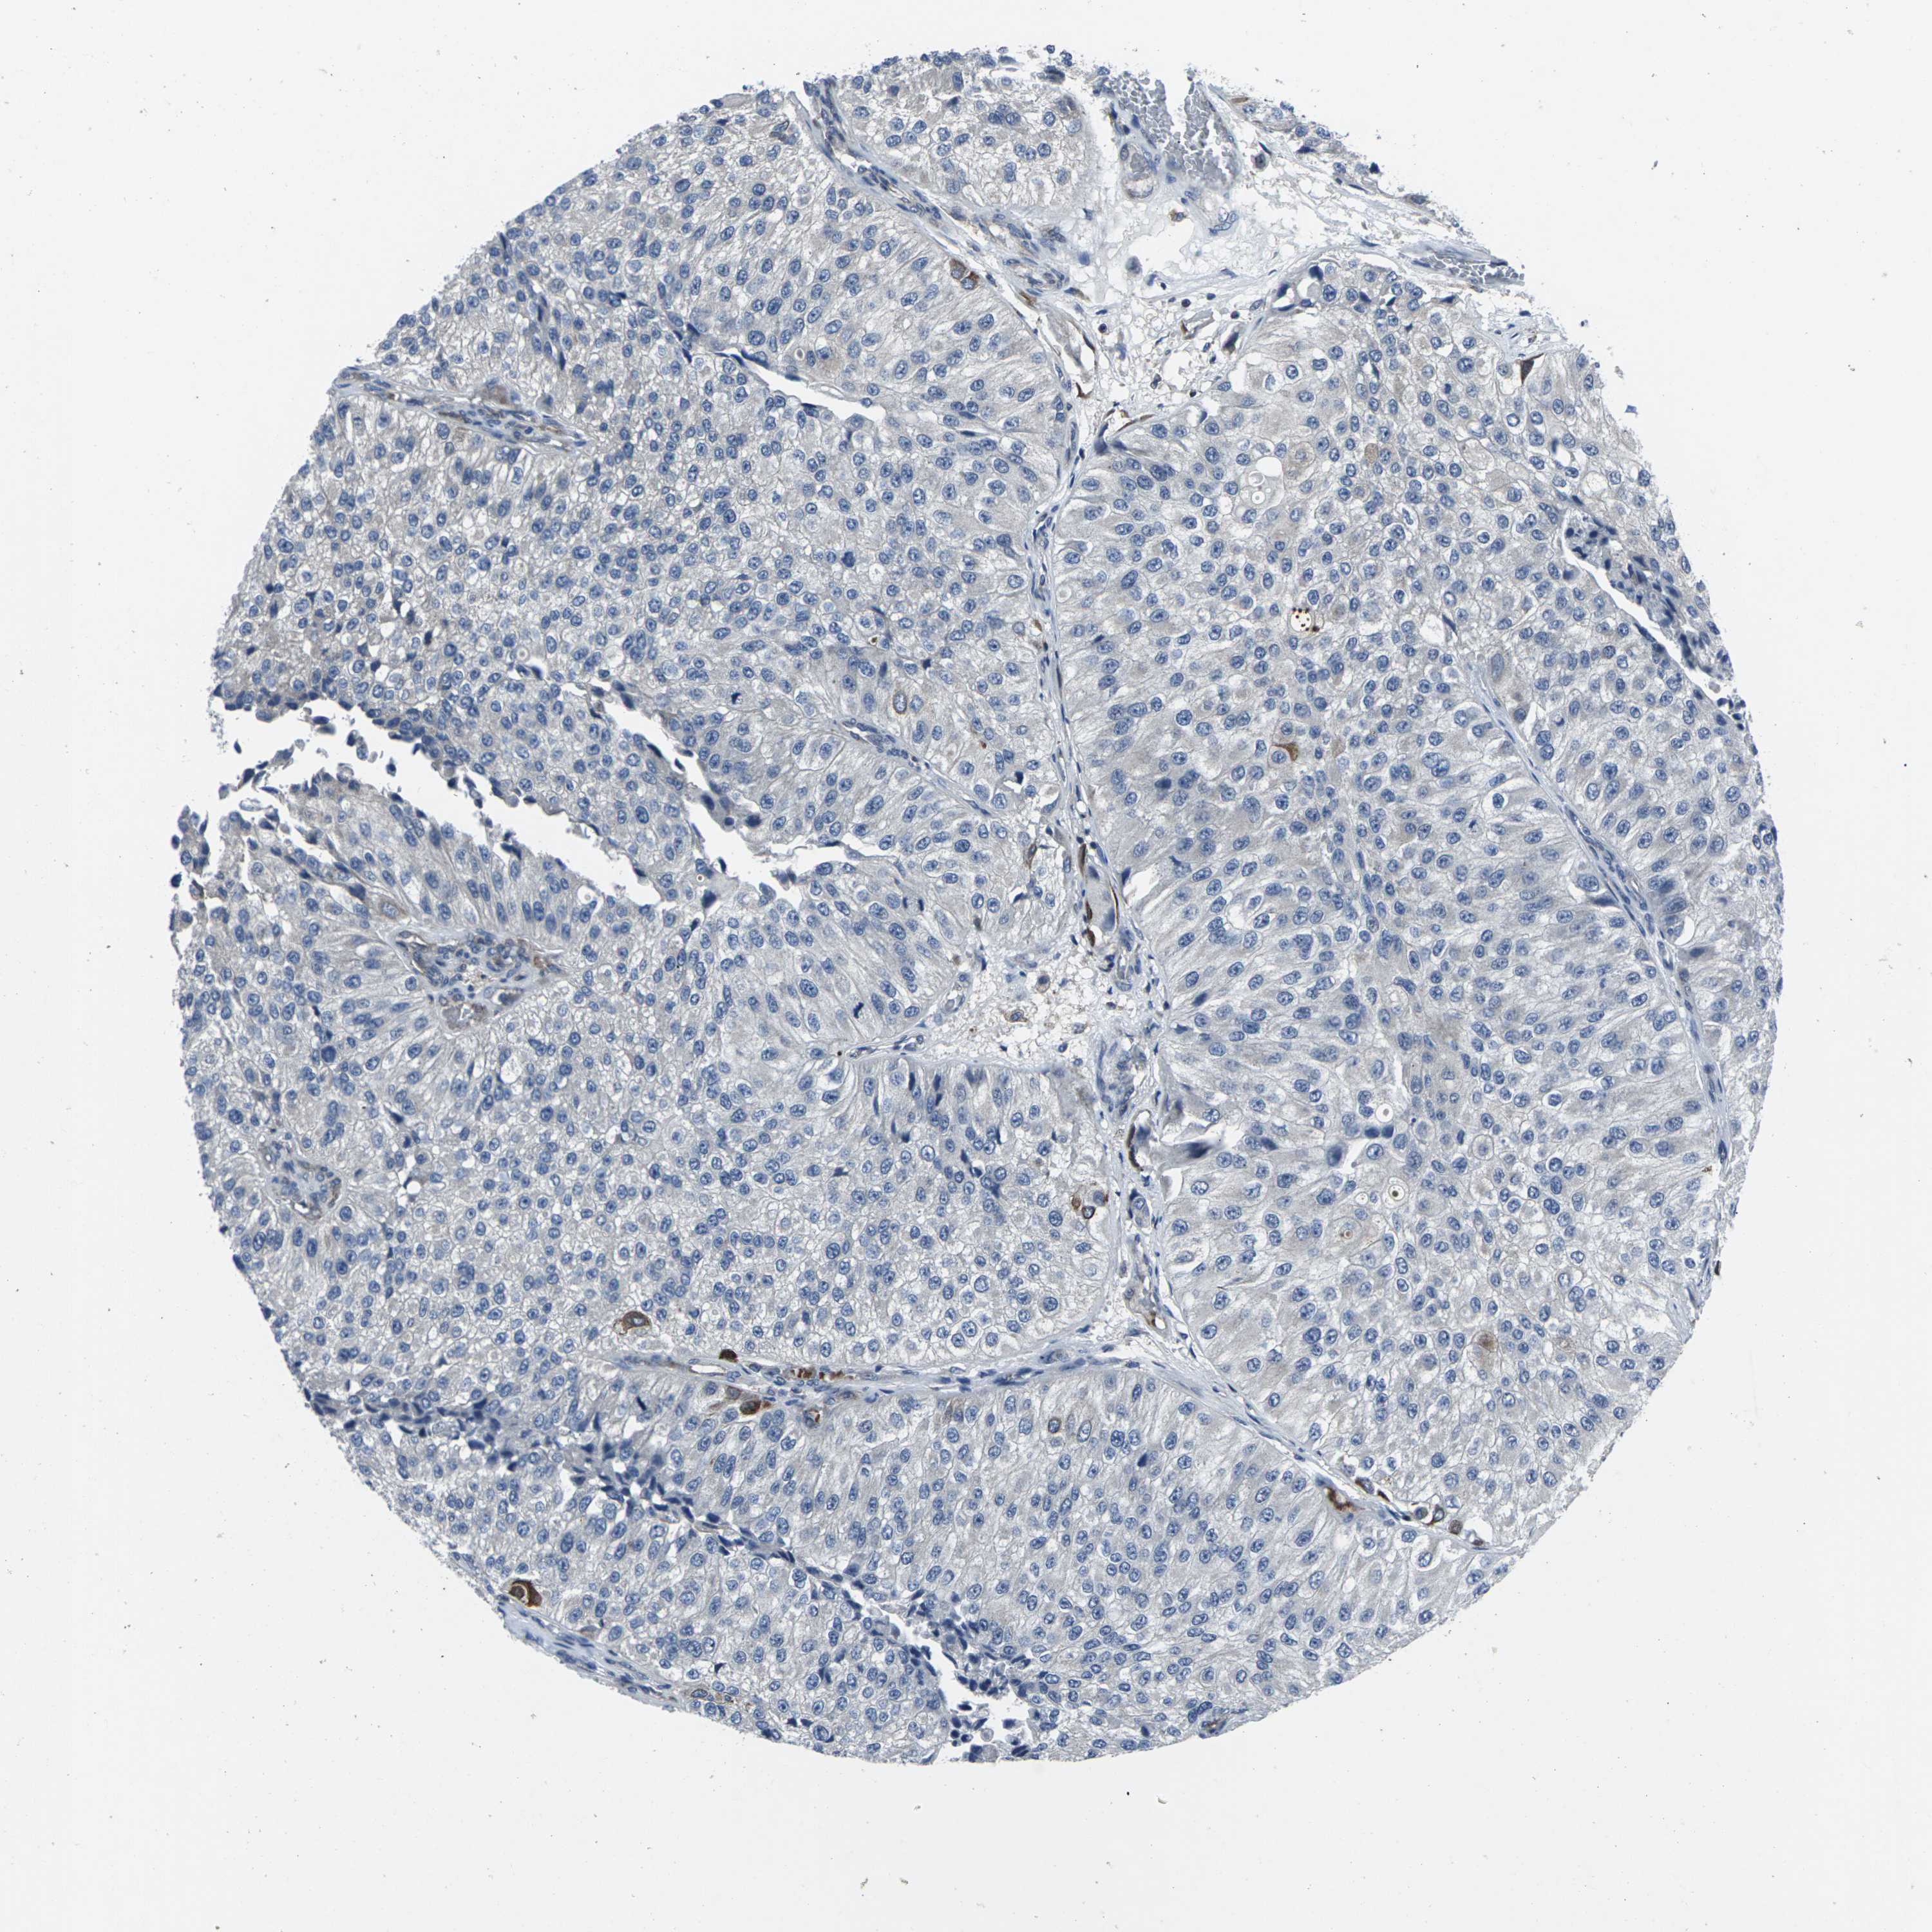

UROTHELIAL CANCER - Protein expressioni

A mouse-over function shows sample information and annotation data. Click on an image to view it in a full screen mode. Samples can be filtered based on level of antibody staining by selecting one or several of the following categories: high, medium, low and not detected. The assay and annotation is described here.

Note that samples used for immunohistochemistry by the Human Protein Atlas do not correspond to samples in the TCGA dataset.

Antibody stainingi

Antibody staining in the annotated cell types in the current human tissue is reported as not detected, low, medium, or high, based on conventional immunohistochemistry profiling in selected tissues. This score is based on the combination of the staining intensity and fraction of stained cells.

Each image is clickable and will lead to virtual microscopy that enables deeper exploration of all samples and also displays staining intensity scores, fraction scores and subcellular localization as well as patient and tissue information for each sample.

Antibody HPA001860

Antibody CAB013108

Urothelial carcinoma, High grade

Urothelial carcinoma, Low grade